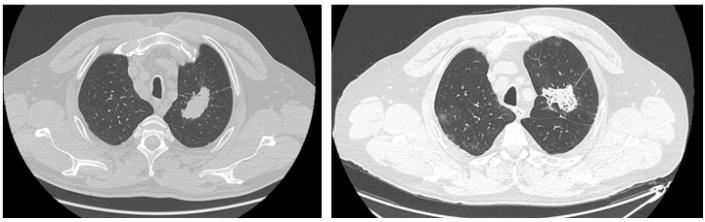

The publication describes the case of a 65-year-old patient with diagnosed lung adenocarcinoma with a L858R activating mutation in exon 21 of the EGFR gene, qualified for treatment with the EGFR tyrosine kinase inhibitor - erlotinib, who was infected with SARS-CoV-2 virus. Due to the infection, it was decided to suspend the treatment for a period of 2 weeks. The passage of SARS-CoV-2 infection did not destabilize the disease. The mild course of the infection prevented the patient from developing more severe complications requiring hospitalization, so there was no reason to discontinue IKT therapy for a longer period of time.